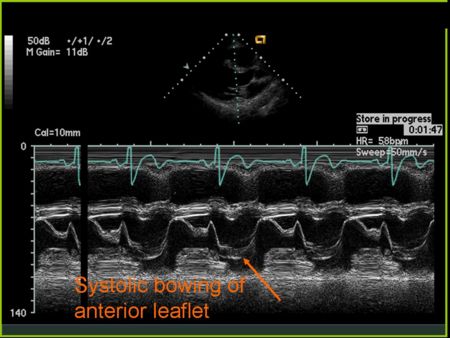

M Mode in Mitral Valve Prolapse

- Systolic bowing of the posterior mitral valve leaflet